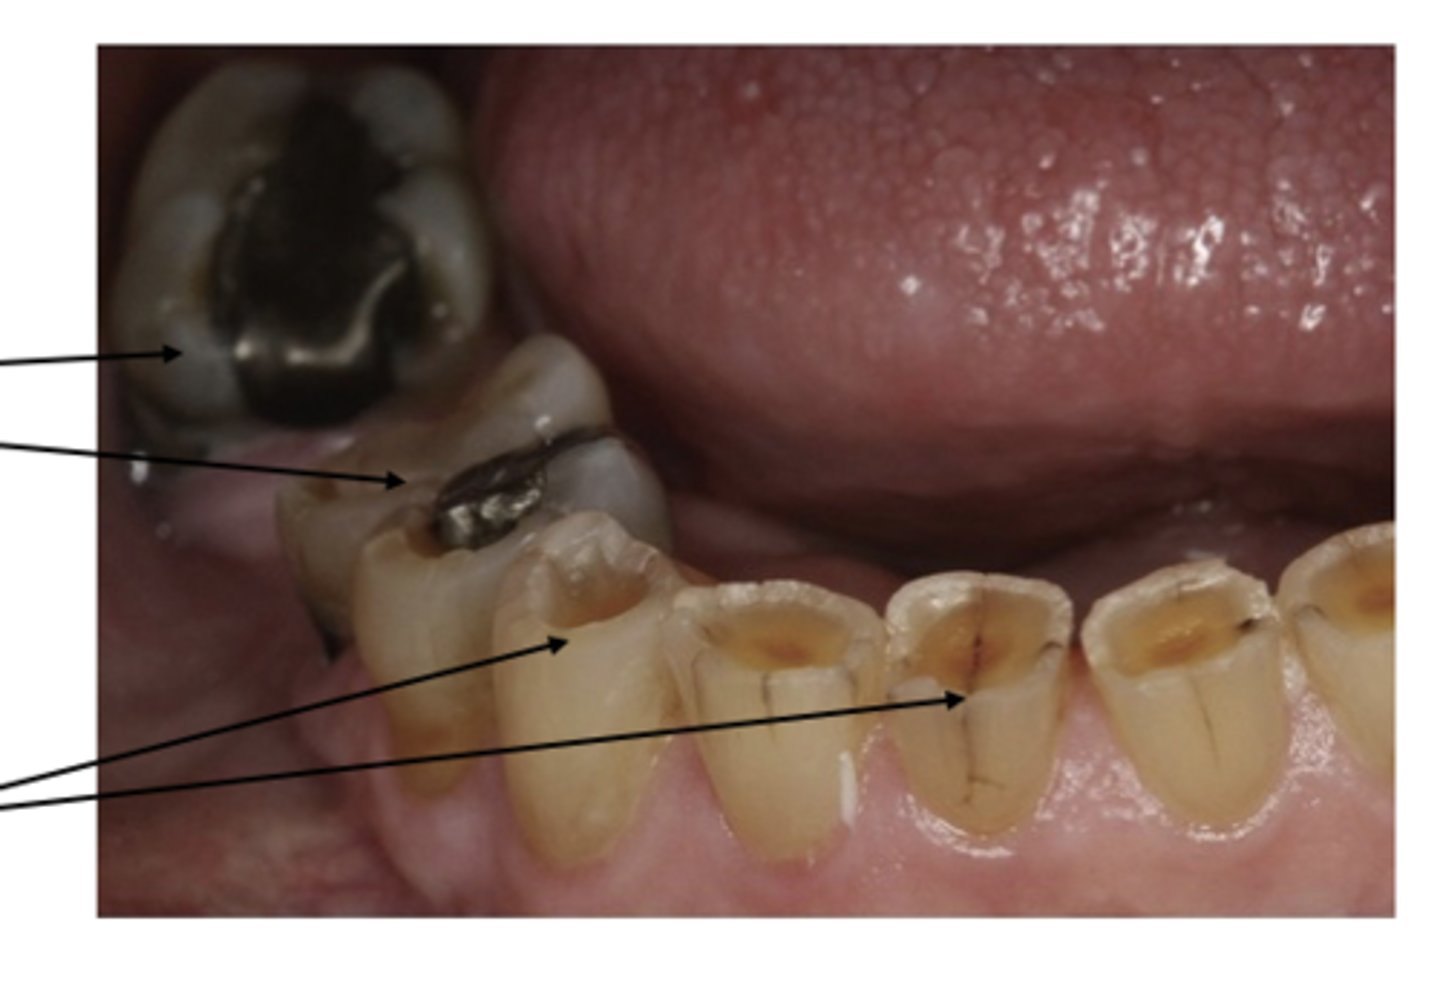

erosion of teeth

yellow brown dentition

Bulimia

Severed acid reflux

<p>yellow brown dentition</p><p>Bulimia</p><p>Severed acid reflux</p>